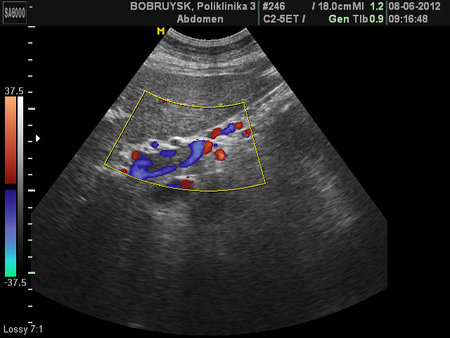

Неполный тромбоз воротной вены и ее ветвей

- Порто-портальные коллатерали

У нас в хирургической клинике пилетромбоз чаще всего случается на фоне панкреатитов. Особенностью этих тромбозов является их слабая регрессия; чаще всего они не реканализируются, а кровоток частично восстанавливается через венозные коллатерали.